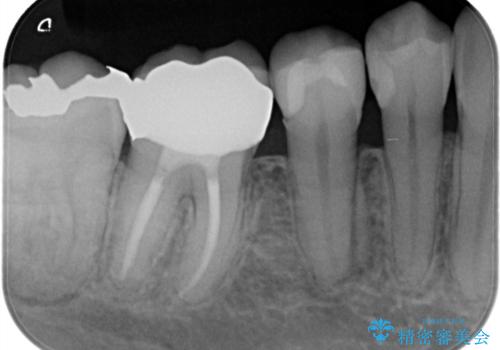

- 虫歯の治療を主訴に来院されました。

奥歯は不可逆性歯髄炎の診断のもと、根管治療を行なった後、被せ物の治療を行なっております。

根管治療を行なった歯は被せ物を使用することで、破折しづらくなります。